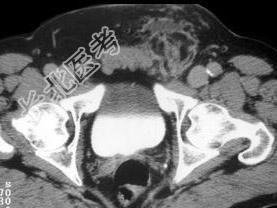

- 单项选择题男,62岁, 左腹股沟可触及肿块,结合所示图像, 正确答案是 ( )

A、斜疝

B、精索脂肪肉瘤

C、淋巴瘤

D、黑色素瘤

E、以上都不是